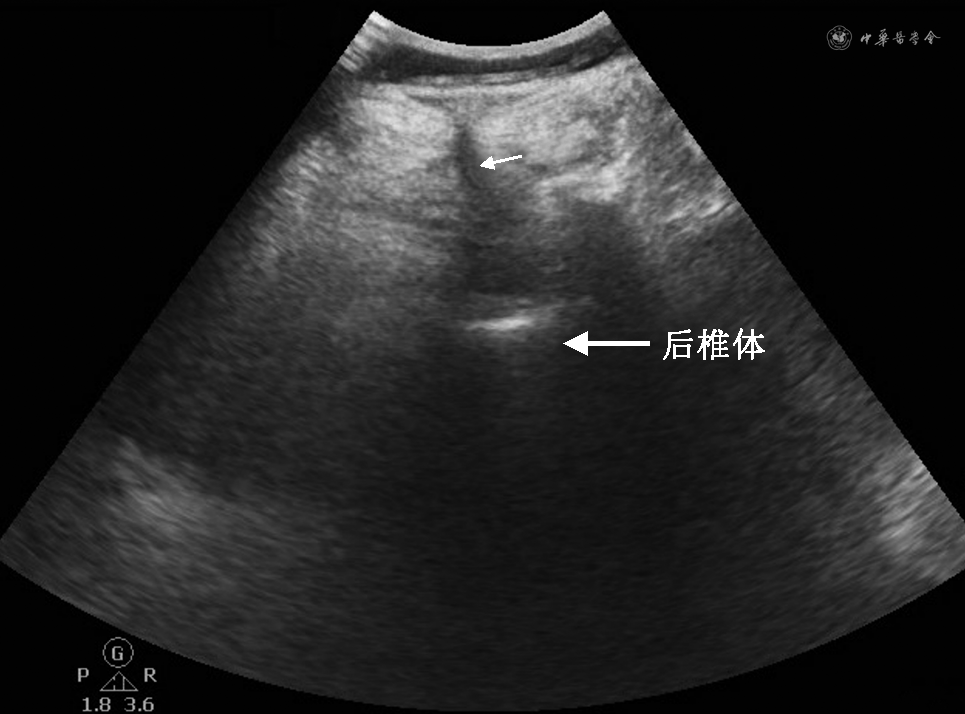

患者于入院后第5天凌晨出现规律宫缩,常规监测心率、血压及氧饱和度(SpO2),鼻导管吸氧(3 L/min),开放静脉通路。入室血压117/64 mmHg(1 mmHg=0.133 kPa),心率81次/min,SpO2 100%。采取左侧卧位,屈膝屈髋位,采用飞利浦CX50可移动实时三维超声系统行超声检查,探头频率 1~5 MHz。超声探头平行于脊柱,在矢状位可见腰1~腰4(L1~L4)棘突向左倾斜,L1~L4椎间隙超声显示不清楚。经矢状位和冠状位反复扫查后,在正中线向左0.5 cm处可见腰4~腰5(L4~L5)椎间隙,在冠状位超声图像下未见明显黄韧带,仅可见椎体,在此处做好标记(图1)。选择L4~L5间隙为穿刺间隙,从标记处置入18 G硬膜外穿刺针,向患者右侧稍微调整进针方向,硬膜外针在距皮肤4.5 cm左右时到达硬膜外腔,并向头侧置入带有钢丝的20 G硬膜外导管,导管深度3 cm,回抽无血液和脑脊液,固定导管。平卧后经硬膜外导管给予试探剂量1.5%利多卡因3 ml(内含1∶200 000肾上腺素),5 min之内患者未出现头晕、耳鸣、舌头发麻等局部麻醉药中毒反应以及低血压等全脊髓麻醉表现,硬膜外腔给予0.1%罗哌卡因和舒芬太尼0.5 μg/ml混合液5 ml,10 min后利用针刺法测定麻醉平面,双侧均为T12,双下肢无发麻和运动障碍,再次追加混合液7 ml,10 min后测定麻醉平面,双侧均为T8,患者诉双下肢麻木,但无运动障碍及其他不适。硬膜外导管连接装有以上混合液的自控硬膜外镇痛泵,设置背景剂量为8 ml/h,追加剂量为5 ml/次,锁定时间为20 min,极限量为20 ml/h。在整个分娩过程中,为保证分娩镇痛效果,实时评估并调整给药剂量和速度,产妇宫缩痛明显缓解,视觉模拟疼痛评分2~3分,无明显运动神经阻滞,镇痛期间持续进行心电、血压和胎心监护。产程进展顺利,最终顺产。婴儿1、5、10 min的Apgar评分均为10分。会阴切口缝合后顺利拔除硬膜外导管。术后随访未出现神经系统并发症及其他不适。